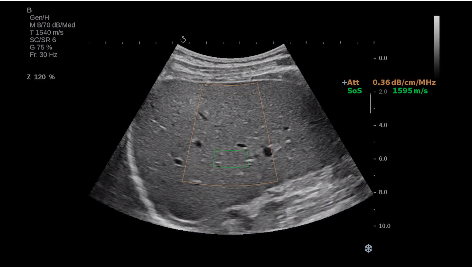

法國聲科影像(SuperSonic Imagine,SSI. Euroniex:FR0010526814)近日發(fā)表公告,宣布其研發(fā)的新一代“極速”超聲成像平臺(UltraFast Imaging),首次實現(xiàn)了肝臟的多項超聲定量評估新指標(biāo)同步檢測,包括:Att PLUS,SSp PLUS和Vi PLUS等,基本涵蓋肝臟相關(guān)病理變化指征的如纖維化、脂肪變、炎癥等。據(jù)悉,此多項新技術(shù)新將搭載于新Aixplorer系列E超系統(tǒng)。

E超相關(guān)技術(shù)已被多項多中心大樣本研究證實對于肝纖維化無創(chuàng)評估有重要意義,同時也可全面應(yīng)用于乳腺、甲狀腺、肝臟、前列腺、肌骨、婦科等全身各組織器官的定量評估和鑒別診斷。在慢性肝臟方面,聲科E超的肝臟相關(guān)定量診斷技術(shù)集,于2018年獲得美國FDA認(rèn)證,成為FDA歷史上首次獲批的單病種超聲全面定量解決方案。

E超是在原有B超、彩超(彩色多普勒CDFI)基礎(chǔ)上研發(fā)成功的新一代超聲剪切波彈性成像系統(tǒng),是一種能夠全面應(yīng)用于表淺組織、腹部臟器,血管等方面的組織彈性成像技術(shù)。根據(jù)組織硬度彈性值的不同,有效鑒別實性腫瘤的良惡性。對于惡性病變的診斷具有較高的特異性和敏感性,尤其對于甲狀腺、乳腺、前列腺等小器官,能夠完成常規(guī)超聲不能完成的組織定量分析,可以實時、全幅、全定量獲得組織彈性(硬度)信息,為鑒別腫瘤的良惡性提供客觀、量化的診斷依據(jù)。